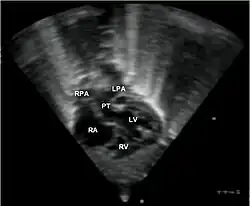

Transpozice velkých tepen je vrozená vada, při které je systémový a plicní krevní oběh rozdělen na dva paralelní oběhy. Hlavní tepny odstupují z nepatřičných komor a tím se tvoří dva uzavřené okruhy. Neokysličená žilní krev ze systémového řečiště prochází pravou síní, komorou a aortou zpět do systémové cirkulace. Okysličená krev z plic jde levou síní, komorou a plicnicí zpět do plic. Tato vada je slučitelná se životem pouze za přítomnosti defektu septa síní, defektu septa komor či persistující tepenné dučeje. V těchto případech koluje v systémovém oběhu smíšená krev. Když je přítomen defekt septa, jsou děti méně cyanotické, rychleji ale dochází k rozvoji srdečního selhání a k vývoji plicní hypertenze. Kombinace transpozice + defekt septa + stenóza plicnice způsobuje cyanózu, ale k selhání či k plicní hypertenzi nedochází.